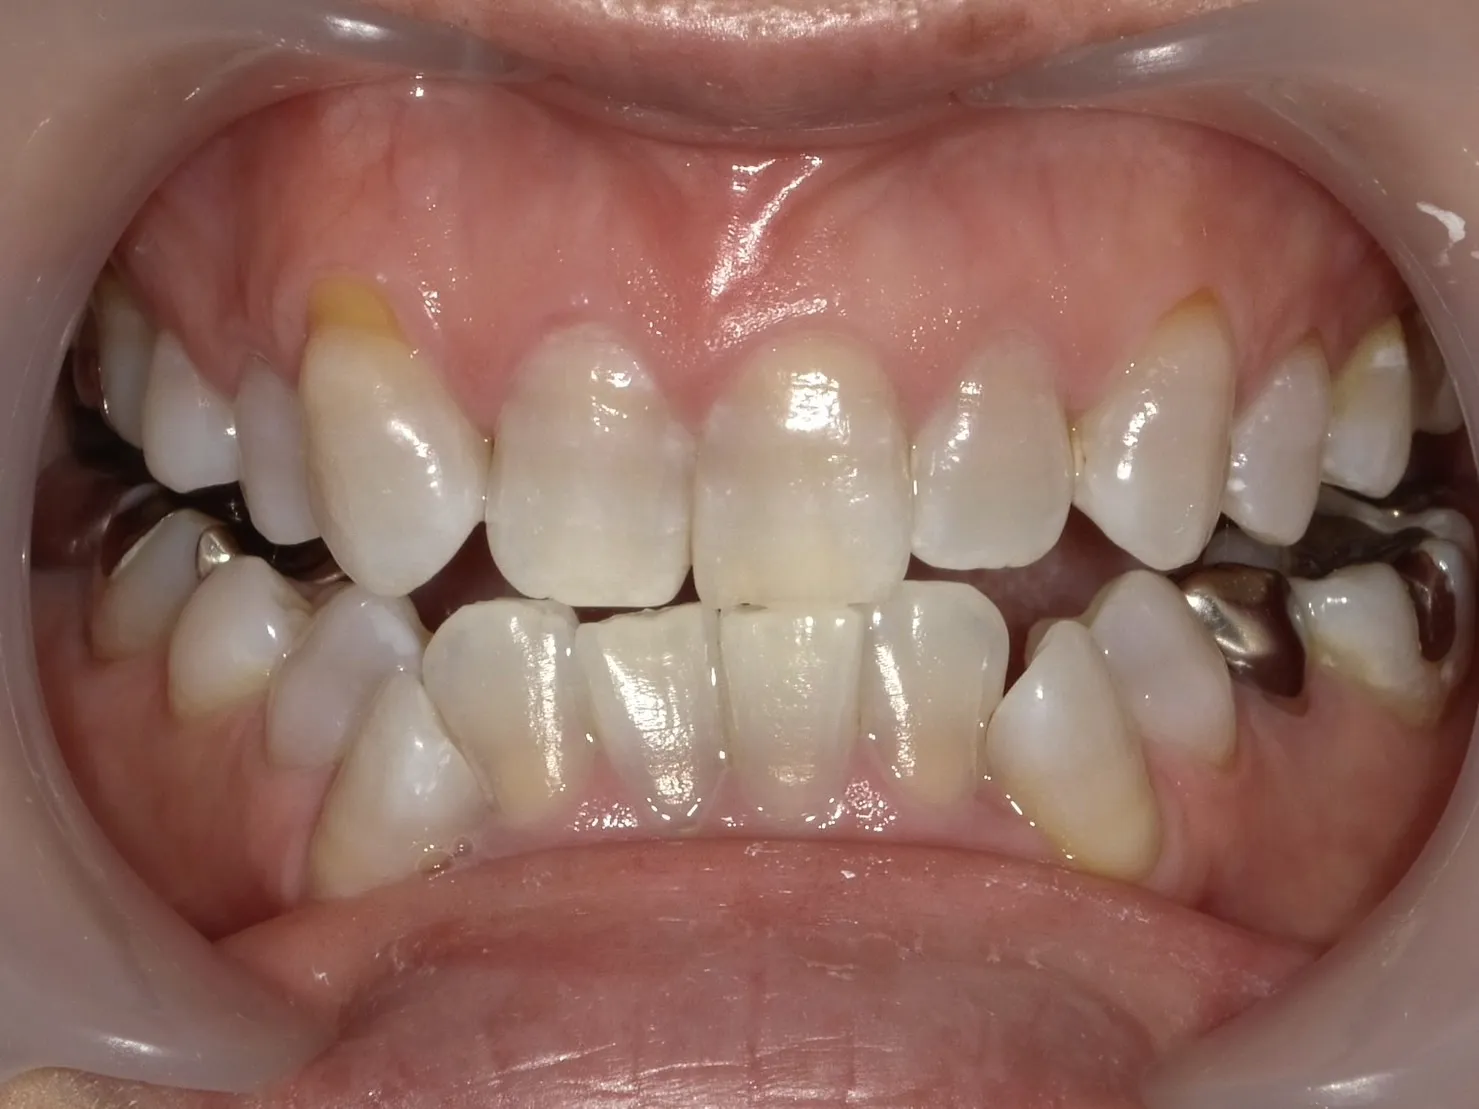

テトラサイクリン歯とは

テトラサイクリン歯とは、テトラサイクリン系抗生物質の服用によって引き起こされる歯の着色の一種です。

この状態は、特に幼少期にこの薬を服用した場合に見られることが多く、歯の発達に影響を与えることが知られています。

テトラサイクリン歯の特徴

深い着色

テトラサイクリン歯は、黄色から茶色、時には灰色の着色を示すことがあります。

この着色は歯の表面だけでなく、内部にまで及ぶことが特徴です。

不均一な着色パターン

テトラサイクリン歯の着色は歯全体に均等に現れるわけではありません。

歯によってはバンド状、斑点状、または不規則なパターンで現れることが特徴です。